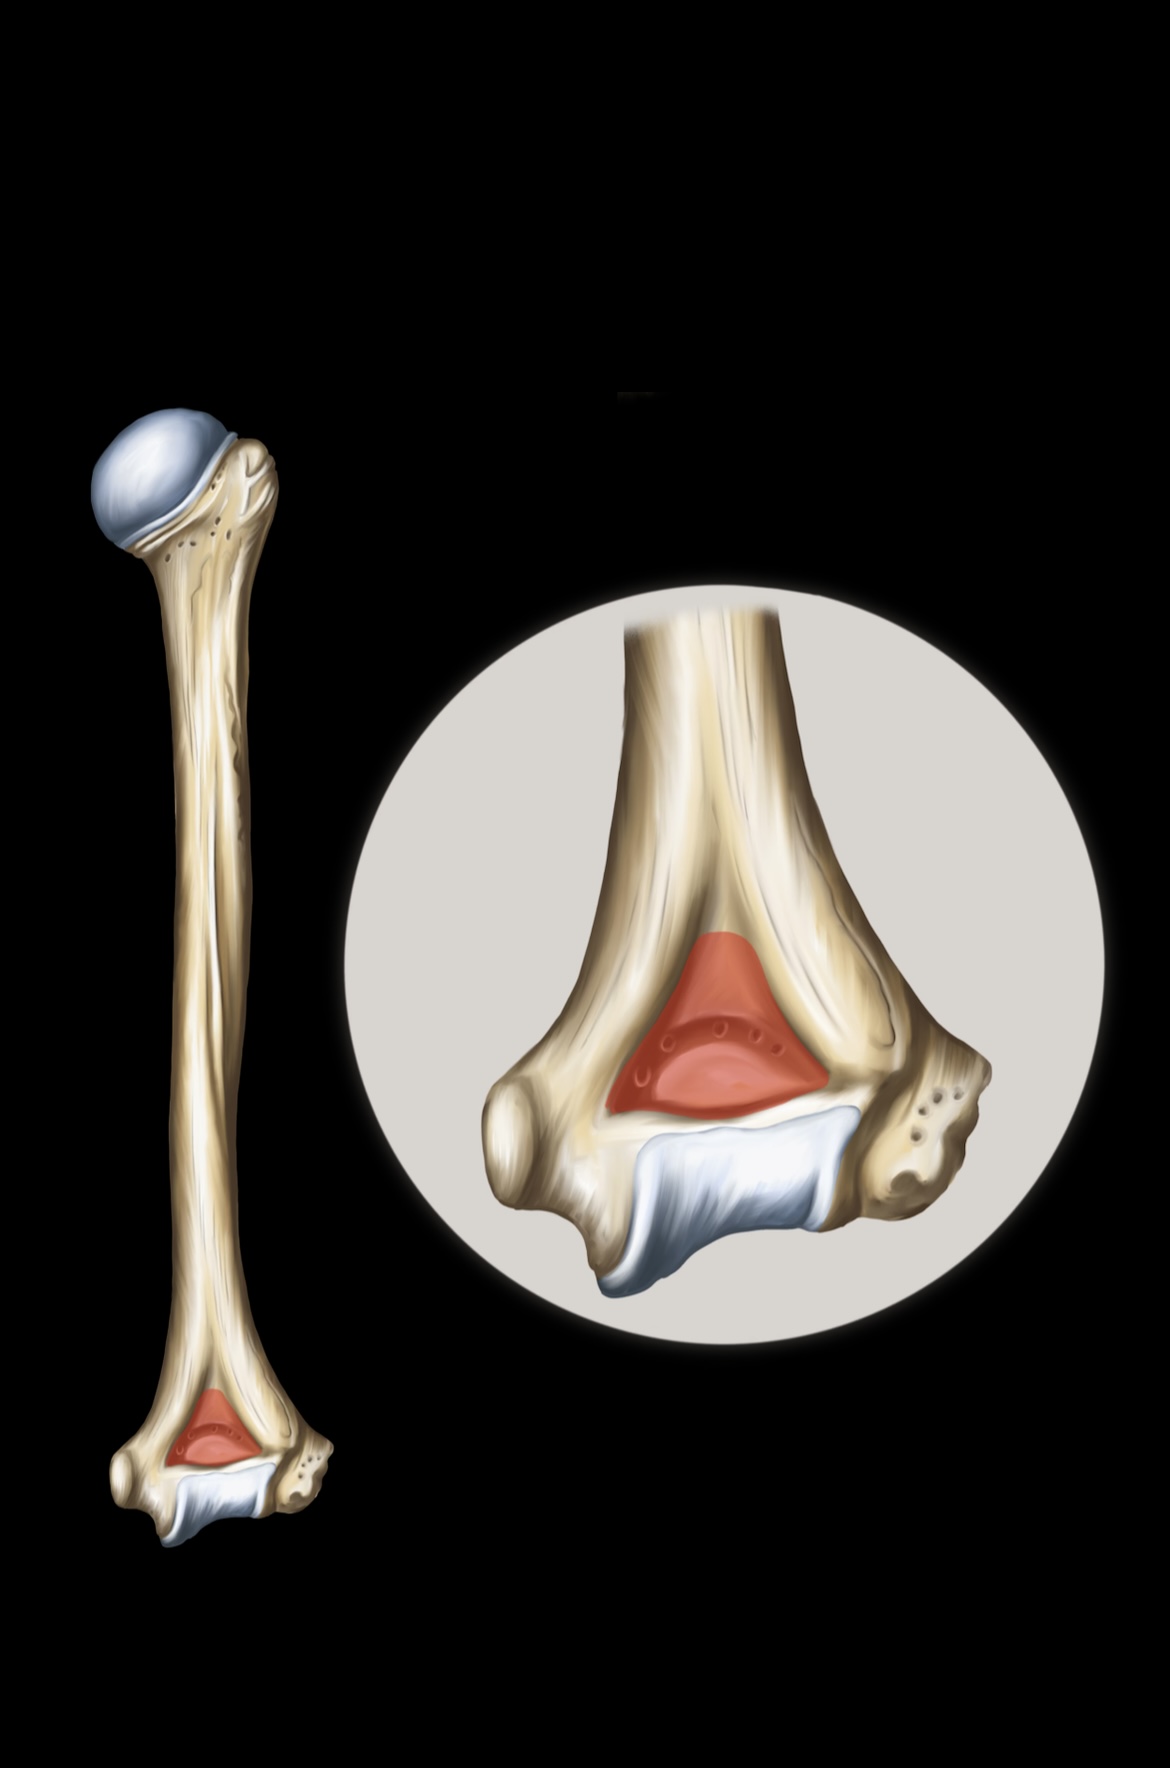

Humerus

Lateral Epicondyles of the Humerus

Medial Epicondyles of the Humerus

Ulna

Olecranon

Trochlear Notch

Ulnar Head